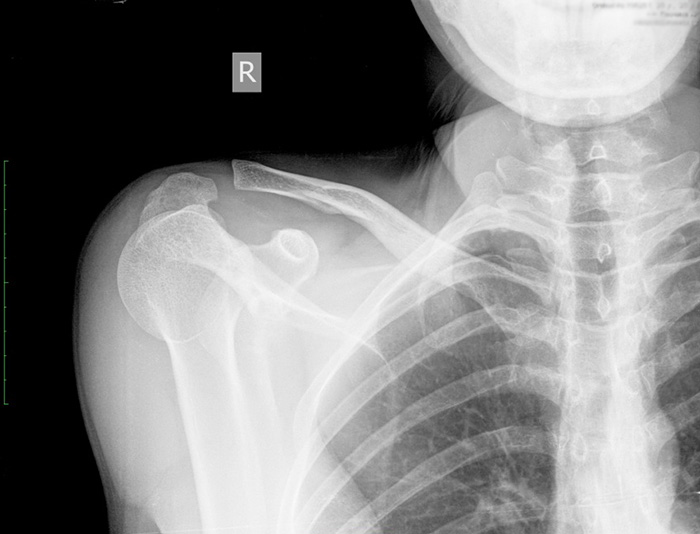

• Перелом ключицы: самая частая причина боли, которая весьма ощутима из-за находящихся поблизости нервных пучков. Даже залеченный перелом при возникновении костной мозоли может продолжать вызывать болевые ощущения.

• Рентгенография ключицы: при переломах является самым недорогим и эффективным методом диагностики.

Наиболее распространенная травма – перелом костной ткани. Диагностируется в 17 процентов переломов. Причина возникновения: прямой удар или падение на поставленную перед собой руку.

Ключица соединяется с мышцами шеи и плечевого пояса, поэтому при ее переломе может наблюдаться смещение отломков. Недуг проявляется:

• болью;

• явным нарушением костной ткани, смещением отломков;

• хрустом и болью при малейшем движении;

• постепенным возникновением и увеличением отечности в районе перелома;

• синяками;

• невозможностью поднимать конечность.

Эти признаки являются характерными и помогают скорее диагностировать болезнь.

Важно! Если в ключице образовалась трещина, надкостница не травмируется и концы кости не смещаются.

Для диагностики травмы используют рентгенографию.

Терапия основывается на типе перелома, могут использоваться консервативные и оперативные методы. Чаще всего прибегают к хирургии: отломки фиксируют спицей. После такой операции пациент чувствует себя намного лучше и быстрее восстанавливается.

Если использование спицы невозможно, поврежденный участок фиксируют повязкой и гипсом примерно на два месяца.

Переломы ключицы

Симптомы перелома сложно спутать с чем-то другим, ведь появляются они преимущественно после травм, о которых пациент помнит: удары, толчки, падения на выпрямленные руки или локти. Боль при переломах очень сильная, отечная, появляются синяки, кость может сменить привычное положение.